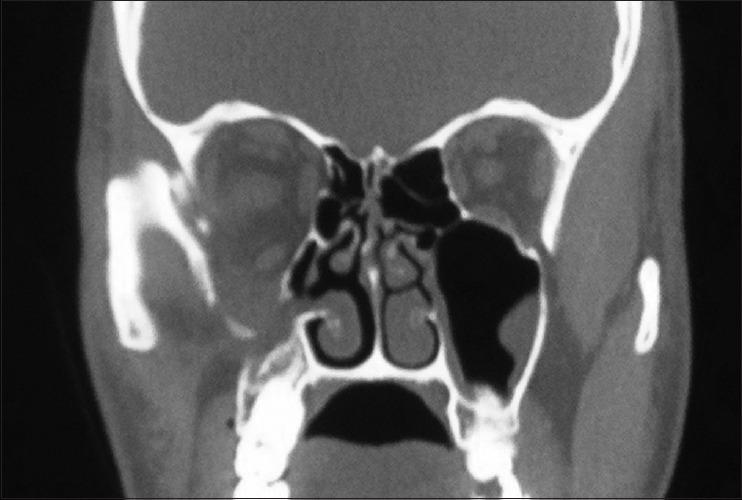

眼眶骨折中骨折类型与眼球内陷及眶内容积矫正的相关性:一项计算机断层扫描研究

Association of fracture type with enophthalmos and intraorbital volume correction in orbital fractures: A computed tomographic study.

METHODS

The investigation was a retrospective cohort study involving CT data of all patients who underwent delayed primary or secondary surgery for orbital/zygomatico-orbital trauma between 2019 and 2021. The sample was divided into three groups 1, 2, and 3: isolated floor, floor and medial wall, and combined orbit and zygomatic complex fractures. The type of orbital fracture was the exposure, while the outcome measures were reduction in enophthalmos and intraorbital volume and linear relationship between the two variables. Data were analyzed for variance between groups and association. Statistical significance was set at < 0.05.

RESULTS

Forty-four patients (3 females and 41 males) with a mean age of 28.6 years were included in the study. Reductions in enophthalmos ( P < 0.001) and intraorbital volume ( P = 0.003) demonstrated significant variance between the groups. For every cubic centimeter of reduction in volume, the reduction in enophthalmos was 0.78 mm ( P < 0.001) in isolated floor fractures, 0.60 mm ( P = 0.013) in combined fractures involving the floor and medial walls, and 0.24 mm ( P = 0.456) in combined fractures of the orbit and zygoma.

CONCLUSION

Correction of enophthalmos strongly depends on the type of orbital fracture. There exists a significant linear relationship between enophthalmos and intraorbital volume in fractures involving the internal orbit.